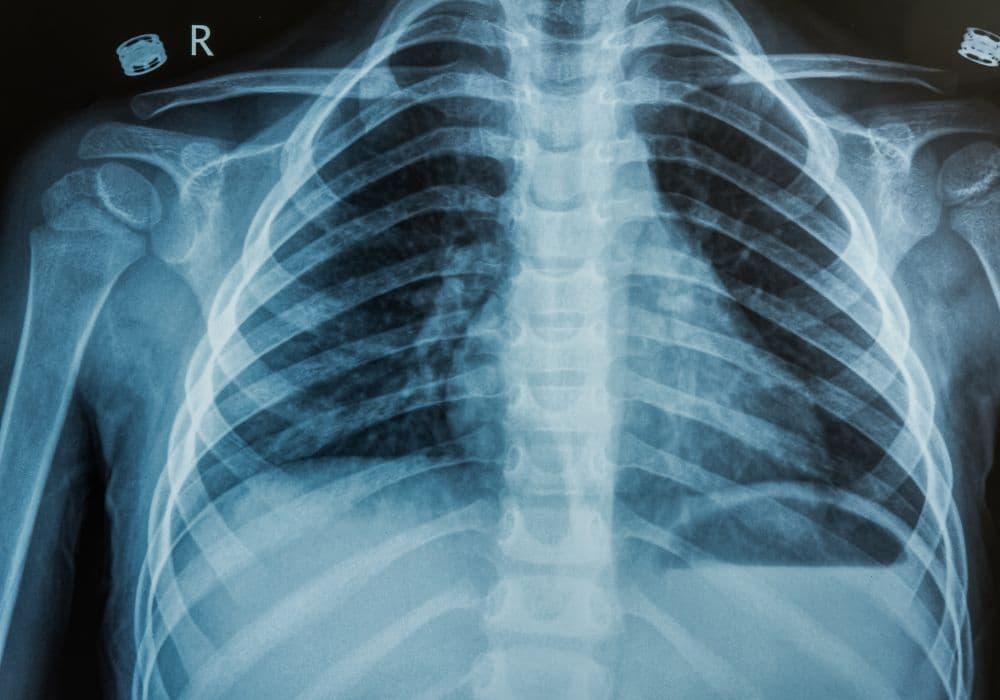

A Glimpse into the Diagnostic Potential of Chest X-rays

Chest X-rays can provide valuable insights into a range of medical conditions. They help diagnose and monitor the following:

- Lung Infections: Chest X-rays can detect infections like pneumonia, bronchitis, or tuberculosis by revealing abnormal lung patterns.

- Lung Tumors: These X-rays can detect tumors or nodules in the lungs that may indicate lung cancer or other abnormal growths.

- Heart Conditions: Chest X-rays can show the size, shape, and position of the heart, aiding in the diagnosis of heart diseases such as heart failure or enlarged heart.

- Chest Trauma: X-rays are used to assess potential injuries like broken ribs, collapsed lungs, or other damage caused by accidents.